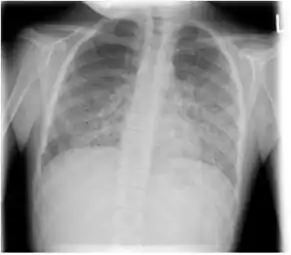

The diagnosis can be confirmed by the characteristic appearance of the chest X-ray and an arterial oxygen level (PaO2) that is strikingly lower than would be expected from symptoms. Gallium 67 scans are also useful in the diagnosis. They are abnormal in about 90% of cases and are often positive before the chest X-ray becomes abnormal. Chest X-ray typically shows widespread pulmonary infiltrates. CT scan may show pulmonary cysts (not to be confused with the cyst-forms of the pathogen).

Chest X-ray of increased opacification (whiteness) in the lower lungs.